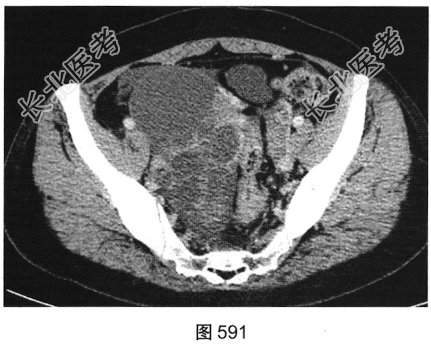

- 多项选择题2.[提示]患者盆腔CT表现见图590、图591。根据以上两幅盆腔CT图像,可以看到哪些阳性表现( )

A、直肠乙状结肠交界区肠管壁厚,强化不均匀

B、双侧髂血管周围多发结节影,可见强化

C、右侧附件区较大囊实性占位性病变,可见不均匀强化

D、右侧附件区多房囊性占位性病变,未见强化

E、盆底腹膜多发结节状软组织影,可见强化

F、盆腔大量积液